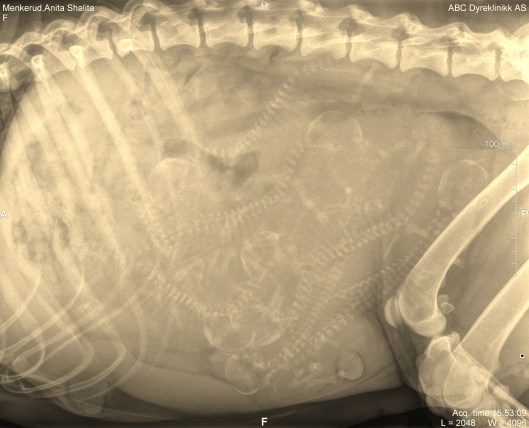

Dyrlege Christopher hos ABC tok bilde av dem og mener det er 7 små på vei. Ikke noe rart jeg har lagt på meg 7,5 kilo og minst 18cm rundt magen. Jeg tror både matmor og jeg gruer oss til opptreningen i november 😂

Røntgen Shalita 190816